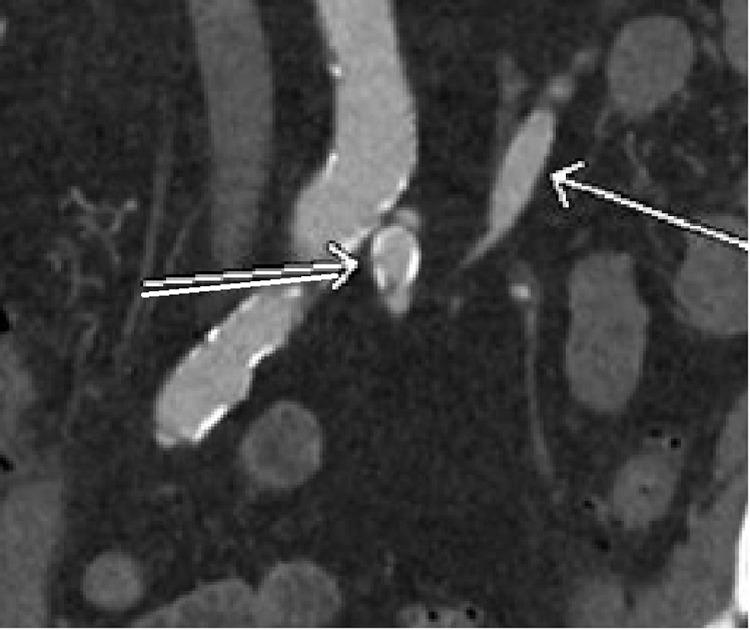

The etiology of large artery aneurysms has long been established as secondary to atherosclerotic disease and degenerative changes in the vessel walls. Less common, are aneurysms of the visceral arteries; the splanchnic and renal arteries. Rarer yet, are inferior mesenteric artery aneurysms, accounting for approximately 1% of visceral artery aneurysms. While causes range from inflammatory to congenital disease, a proposed etiology of proximal, solitary inferior mesenteric artery aneurysms, is correlated to the "jet disorder phenomenon," first described in a 1990 case report by Sugrue, and Hederman. This paradigm states that aneurysm formation may occur secondary to celiac and superior mesenteric artery occlusion, causing increased, and turbulent arterial flow distally. We present a case that demonstrates a small inferior mesenteric artery aneurysm without findings of celiac or superior mesenteric artery stenosis or occlusion. This patient did, however, have a large thrombosed common hepatic artery aneurysm which may serve as an alternate cause of jet disorder phenomenon. The findings in this case offers support for focused screening of proximal arterial vasculature when an inferior mesenteric artery aneurysm is encountered.

大动脉动脉瘤的病因长期以来一直被认为是继发于动脉粥样硬化疾病和血管壁的退行性变化。内脏动脉的动脉瘤较少见,如内脏和肾动脉。更罕见的是肠系膜下动脉动脉瘤,约占内脏动脉动脉瘤的1%。虽然病因范围从炎症性疾病到先天性疾病,但一种关于近端孤立性肠系膜下动脉动脉瘤的病因假说与“喷射紊乱现象”相关,该现象最早在1990年Sugrue和Hederman的病例报告中描述。该范例指出,动脉瘤形成可能继发于腹腔干和肠系膜上动脉闭塞,导致远端动脉血流增加和紊乱。我们报告一例病例,该病例显示一个小的肠系膜下动脉动脉瘤,未发现腹腔干或肠系膜上动脉狭窄或闭塞。然而,该患者有一个大的血栓形成的肝总动脉瘤,这可能是喷射紊乱现象的另一个原因。该病例的发现为遇到肠系膜下动脉动脉瘤时对近端动脉血管进行重点筛查提供了支持。